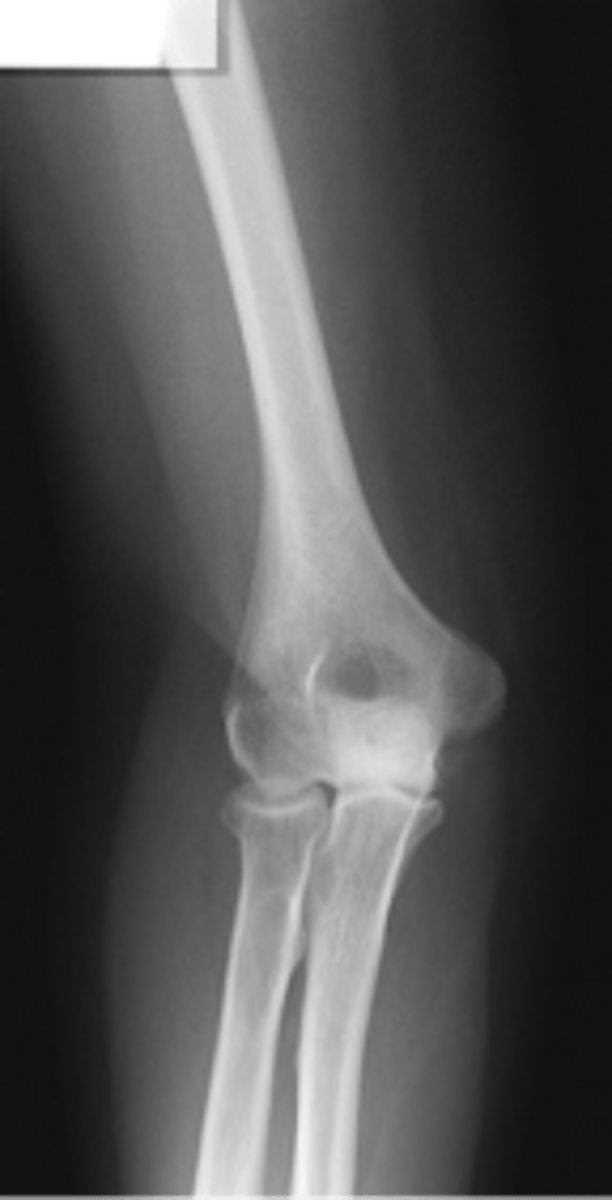

AP Lateral (External) Oblique Elbow

AP medial (internal) oblique elbow